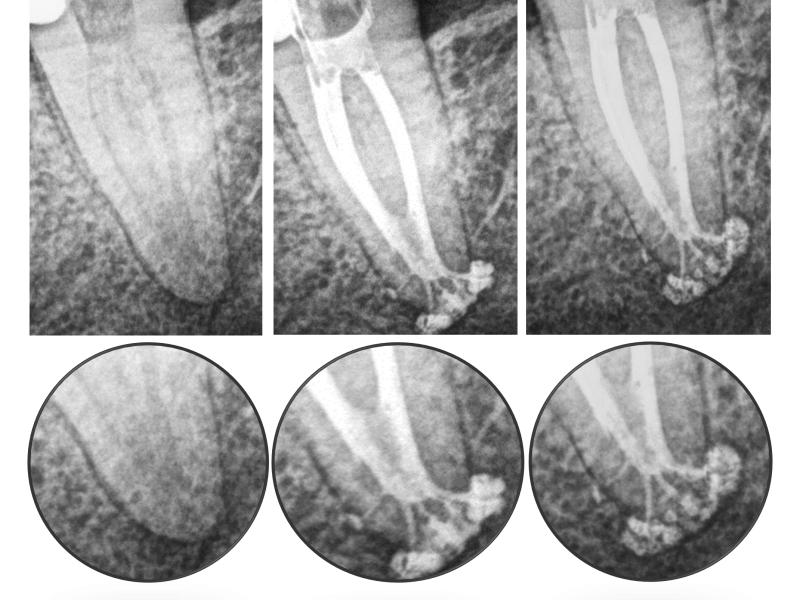

Silver Point Retreatment with Symptomatic Apical Periodontitis

GentleWave

®

G4 with ProControl

™

Karen S. Potter, DDS

View Case Details